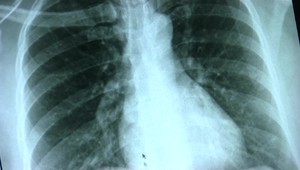

Na rakovinu štítnej žľazy vás môže upozorniť hrča v krku, zmeny hlasu a dokonca aj kašeľ! Zdravie a diagnózy